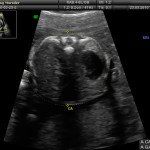

L’ecografia è una tecnica che consente di vedere gli organi del nostro corpo con l’utilizzo di onde sonore ad alta frequenza (ultrasuoni, non udibili dall’orecchio umano) che attraversano i tessuti. La sonda ecografica invia impulsi di onde sonore nel corpo. Quando le onde sonore arrivano al feto mandano degli echi: tali echi (o onde di ritorno) sono trasformati in immagini sul monitor dell’ecografo. Con l’ecografia è quindi possibile osservare in modo dettagliato il feto.

Con l’ecografia transvaginale è possibile vedere dopo circa 3 settimane dal concepimento la camera gestazionale nella cavità uterina. Successivamente è possibile visualizzare l’embrione (3-5 mm.) a circa 6 settimane dall’ultima mestruazione (4 settimane dal concepimento) ed a questo periodo è già visibile l’attività cardiaca fetale Anche i primi dettagli sulla morfologia fetale (polo cefalico, abbozzi degli arti) sono visualizzabili più precocemente con l’ecografia transvaginale, risultando essi visibili intorno a 8-9 settimane.